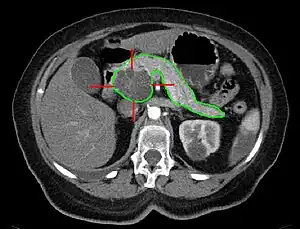

| MRI - cancerous pancreatic cyst | |

A pancreatic cyst is a fluid filled sac within the pancreas.[1] There are several types, some with the potential to become cancerous, and they are commonly found when investigating another problem.[2]

Diagnosis is by medical imaging.[2]